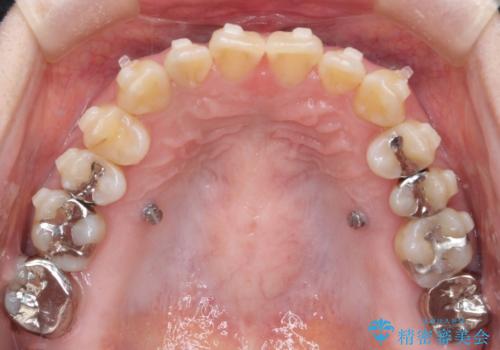

- 上の前歯の捻れと、前歯で物が噛めないことを主訴に来院されました。

前歯の翼状捻転とオープンバイト傾向だったため、インビザラインにて矯正を行いました。右下の奥歯は保存不可だったため、抜歯を行いインプラントにて修復を行なっています。

翼状捻転はインビザラインでは苦手とする動きですが、ここまで綺麗に治すことができました。